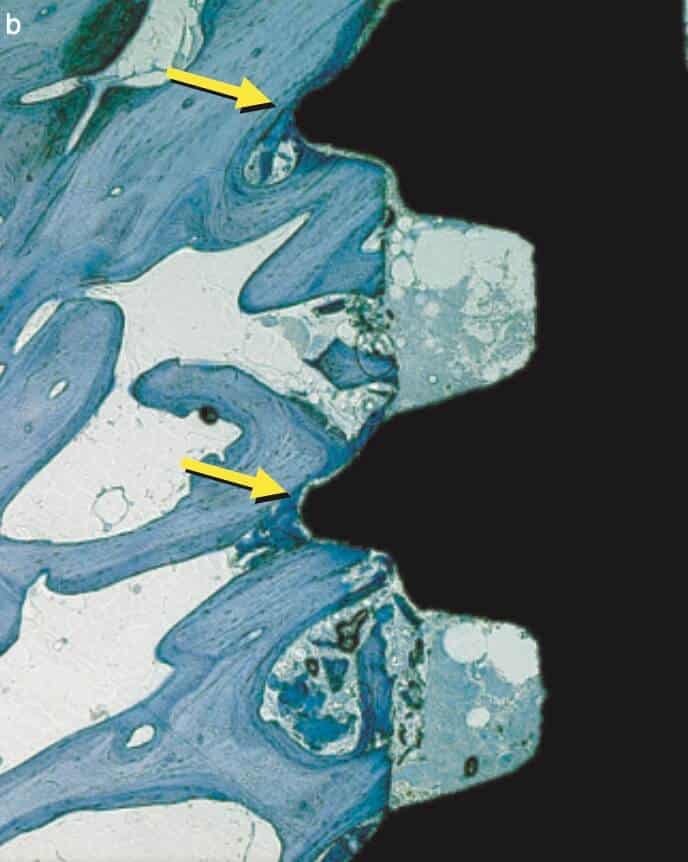

Right after implant placement, friction stability was achieved thanks to the pitches of the threads biting tight into the bone walls, while the non-contact areas filled with blood clot. The big news came however on the 4th day, when an interesting pattern of bone resorption occurred at the coronal side of the pitch! Why resorption? Obviously the compression of the bone there had killed a zone of bone about 50 μm, which was now being cleared away.

And why the top of the pitch and not the bottom? Well, this is actually screw mechanics. Regardless if you work with implants or with IKEA furniture, screws only apply force through the side of the thread which faces their side of insertion. A screw thread has actually only one working side. We learned this well when we were slicing implant-abutment junctions, only to see how little surface of the actual screw is engaging with the implant and always only the coronal part. (We learned a lot by looking at screws that time, but that would be probably a topic for another post). Common engineering never ceises to amaze!

Back to our histology study, the observation of the 4th day was actually an “aha” moment for all. It showed how compression kills bone and initiates resorption early after placement. This observation seen however in isolation made many clinicians to blame extensive threads as “bone killers”, starting the perception of implants with shallow or few threads as being “passive”. (It was also probably the reason why this experimental implant remained forever a dog-implant).

To get the whole picture, we need to look closer at the other side of the coin and see what happens in the no-contact areas. There, at 1 week one could see another exciting development: contact osteogenesis! New mineralized bone was created on the surface of the implant in the empty chamber, where previously only blood clot existed. This was something hardly seen on the smooth surface implants, but was apparent in the SLA implants introducing another factor in the equation, the implant surface.

The collective message of these amazing experiments was the while bone is being cleared at the pitch of the thread, new bone is getting created on the implant surface at the no-contact areas! Surface is a significant factor here, with contact osteogenesis being well established at 2 weeks in humans with SLAactive implants, as documented by another great study by Lang et al (4). Lang as well, noted absence of new bone at the pitch of the thread after 1 week, but significant new bone in non-contact areas, where the “jumping” distance between the implant and the bone was short. Again, this message seen somewhat superficially, lead many to believe that the lower and fewer the implant threads, the better the implant would be, reinforcing the anecdotal concept of “aggressive” and “passive” implants. But as you can’t judge a book by its cover, you shouldn’t also judge an implant by its threads! The missing part here was that an implant with few and shallow threads will be unlikely to offer adequate primary stability!